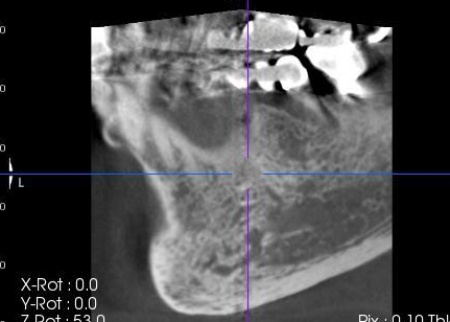

| 行ったご提案・治療内容 | まずは左下奥歯に装着されていた被せ物を慎重に除去し、歯根の状態を直接確認します。 その結果、歯根破折が明確に認められたため、歯の温存は困難であると判断しました。 抜歯後の治療として、以下2種類の方法を提案しました。 ①延長ブリッジ ②インプラント それぞれのメリットとデメリットを丁寧にお伝えしたところ、患者様は②のインプラント治療を選択されました。 まずは局所麻酔を行い、破折した歯を丁寧に抜きます。 抜歯後は骨の治癒を待つため、約3ヶ月間の経過観察を行いました。 経過観察後、骨の状態が安定したことを確認したら、インプラント体(人工歯根)を顎の骨に埋め込む手術を行います。 手術では、歯茎を切開した骨を露出させ、専用の器具で慎重に穴を形成したうえでインプラント体を埋入します。続いて歯茎を縫合し、インプラント体が骨と結合するまでの期間を設けました。 後日、インプラント体と骨がしっかりと結合したタイミングで、インプラント体の上に土台を装着し、人工の歯を取り付けます。 最後に、装着したインプラントの見た目や使用感、噛む機能の回復などを確認して、治療を終了しています。 |

抜歯後の骨の状態を確認しています。

インプラントの埋入設計をしました。

インプラント体と骨の結合を確認しました。